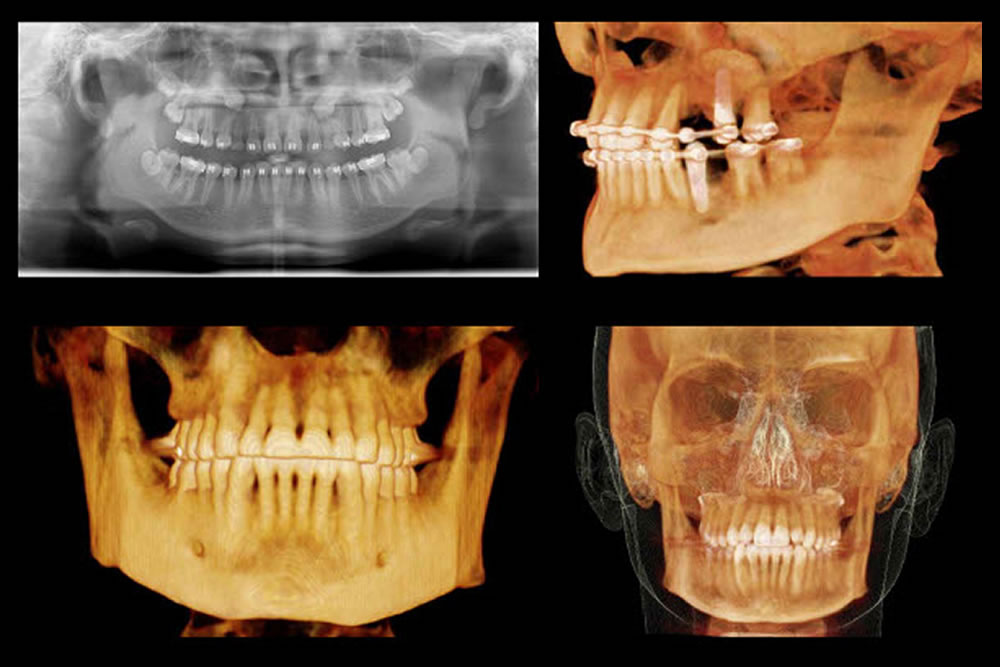

歯科用CTによる立体的な診断を実施

歯科用CTは、歯や顎の骨の状態を三次元的に確認できる検査機器です。

通常のレントゲンでは把握しにくい、歯の根の形や位置関係、顎の骨の厚みや状態、神経や血管の位置といった情報を立体的に確認することができます。

これらの情報は、インプラント治療や根管治療、外科的処置を伴う治療の計画を立案するための資料として活用します。

外科処置のトラブル防止・処置精度の向上につながります

インプラント治療や根の治療、外科的な処置が必要な場合には、治療する部分のすぐ近くに神経や血管が通っていることもあります。

歯科用CTを用いることで、こうした位置関係を事前に確認し、適切な治療計画を立てることができます。当院では、必要に応じて歯科用CTを活用し、患者さまにも画像をお見せしながら、わかりやすい説明を心がけています。